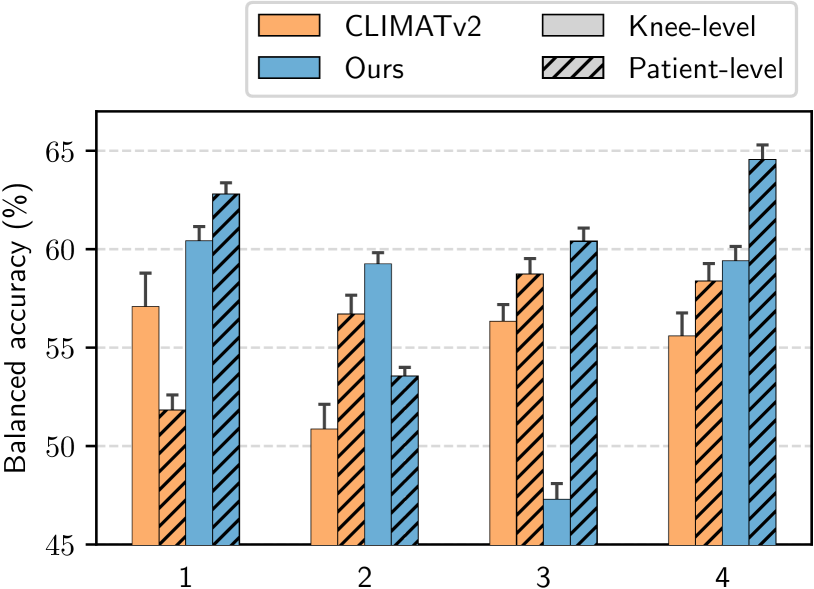

To provide additional insights, we further present the corresponding fine-grained results in Figure 5. Most of the time, patient-level models reduced the standard error in BA and RC of both CLIMATv2 and our RL-based agent. Particularly, at the 1-year time point, our patient-level policy exceeded the patient-level CLIMATv2 with the highest difference by approximately 15% in BA and 60% in RC. Furthermore, the greatest gap between patient-level and knee-level of our method occurred 3 years after baseline by approximately 20% in BA and 40% in RC. In general, our patient-level policy showed substantial improvement compared to other methods most of the time.

| Method | Year(s) | BA(%) | RC(%) | |

| Knee-level | CLIMATv2 | 1 | 57.09 1.69 | 24.29 6.22 |

| 2 | 50.87 1.26 | 23.77 4.30 | ||

| 3 | 56.34 0.84 | 46.15 5.00 | ||

| 4 | 55.60 1.16 | 38.59 4.55 | ||

| Ours | 1 | 60.43 0.72 | 58.98 3.84 | |

| 2 | 59.26 0.57 | 82.92 1.83 | ||

| 3 | 47.30 0.80 | 32.88 0.72 | ||

| 4 | 59.41 0.73 | 38.51 1.95 | ||

| Patient-level | CLIMATv2 | 1 | 51.83 0.77 | 7.55 3.18 |

| 2 | 56.71 0.95 | 42.83 5.97 | ||

| 3 | 58.73 0.79 | 50.58 3.24 | ||

| 4 | 58.38 0.89 | 50.16 4.80 | ||

| Ours | 1 | 62.81 0.57 | 74.08 2.62 | |

| 2 | 53.56 0.44 | 96.98 0.85 | ||

| 3 | 60.40 0.67 | 67.69 1.03 | ||

| 4 | 64.55 0.74 | 55.94 1.56 |